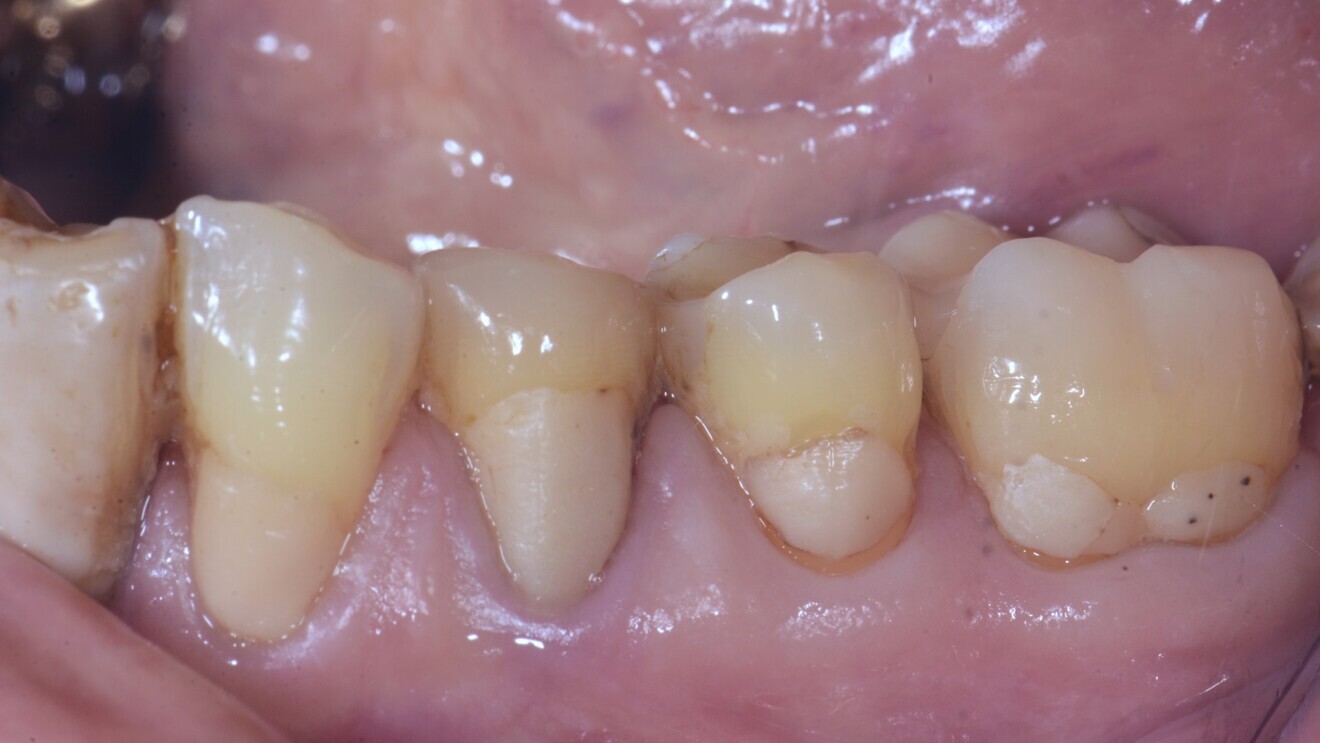

Fig. 1: Multiple cervical non-carious lesions prior to treatment. (All images courtesy of Dr Matteo Basso, Italy)

Cervical lesions (Figs. 1–3)

The cervical placement of glass ionomers, especially resin-modified glass ionomers, has a long tradition and is backed by a wealth of clinical studies demonstrating the usefulness of this material for this purpose. Resin-modified glass ionomers have consistently outperformed alternative materials when it comes to survival and success of cervical restorations.5 For glass hybrids, two randomised trials comparing this material against resin composites were identified.